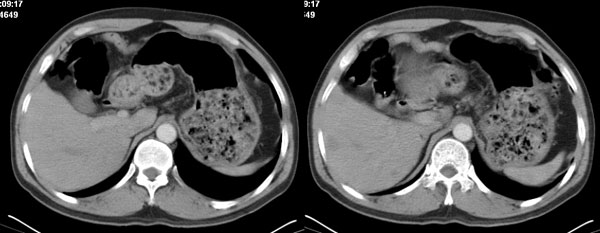

李**,男,46岁,便血1天入院,慢性贫血貌,腹平、软,剑突下压痛,肠鸣音稍活跃,hb大于1g/l,胃镜:慢性浅表性胃炎,b超:1肝内多发性占位 2腹腔内囊性肿块 ,肝内圆形影平扫ct值42.9,动脉期48.6,静脉期58.2,延迟期62.2

影像学表现:1 腹腔前中部、胰腺前方囊实性病灶(个人认为确定有否实性成分存在这是关键,涉及到鉴别诊断,如果是口服阳性造影剂则可明确左侧是不是小肠了),囊性部分囊壁不均,实性部分有强化,与小肠关系较密切,局部小肠受推移;与胰头、胃后壁均有脂肪间隙存在;2 胰腺无异常改变,胰周无渗出;3肝后段包膜下2个小圆形低密度灶,从图像和楼主提供的ct值来看有轻度强化,灶周无片状强化,不似单纯囊肿及肝癌、炎性病变表现;4 腹膜后及腹腔内无淋巴结肿大。

胰腺边界清晰,胰周筋膜不厚,胰周脂肪密度无明显增高;其前方囊实性病灶,边界清晰,增强后实性部分轻度强化;肝内多发边界清晰低密度影,增强后无明显强化(平扫ct值42.9,动脉期48.6,静脉期58.2,延迟期62.2)。

原因:胰头前方,前上腹部巨大囊实性肿物,与小肠关系密切,与胰头及胃壁之间脂肪间隙存在,囊壁不均匀,部分强化,占位效应明显,小肠上段扩张,十二指肠及胃腔内大量食物存留,说明上消化道有部分梗阻。因此,考虑来源于肠道的肿瘤。再结合其病史及肝内改变,这样考虑更有道理。